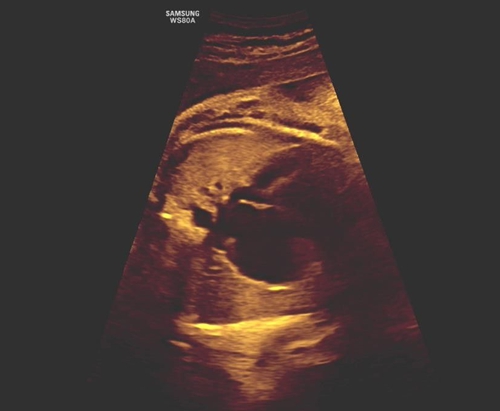

通過(guò)清晰的超聲圖像與精準(zhǔn)的血流動(dòng)力學(xué)評(píng)估,團(tuán)隊(duì)明確觀察到:胎兒卵圓孔通道無(wú)血流信號(hào)通過(guò),同時(shí)伴有右心房室明顯增大、三尖瓣大量反流等間接征象,最終精準(zhǔn)確診“胎兒卵圓孔早閉”,并準(zhǔn)確評(píng)估出心功能受損程度。